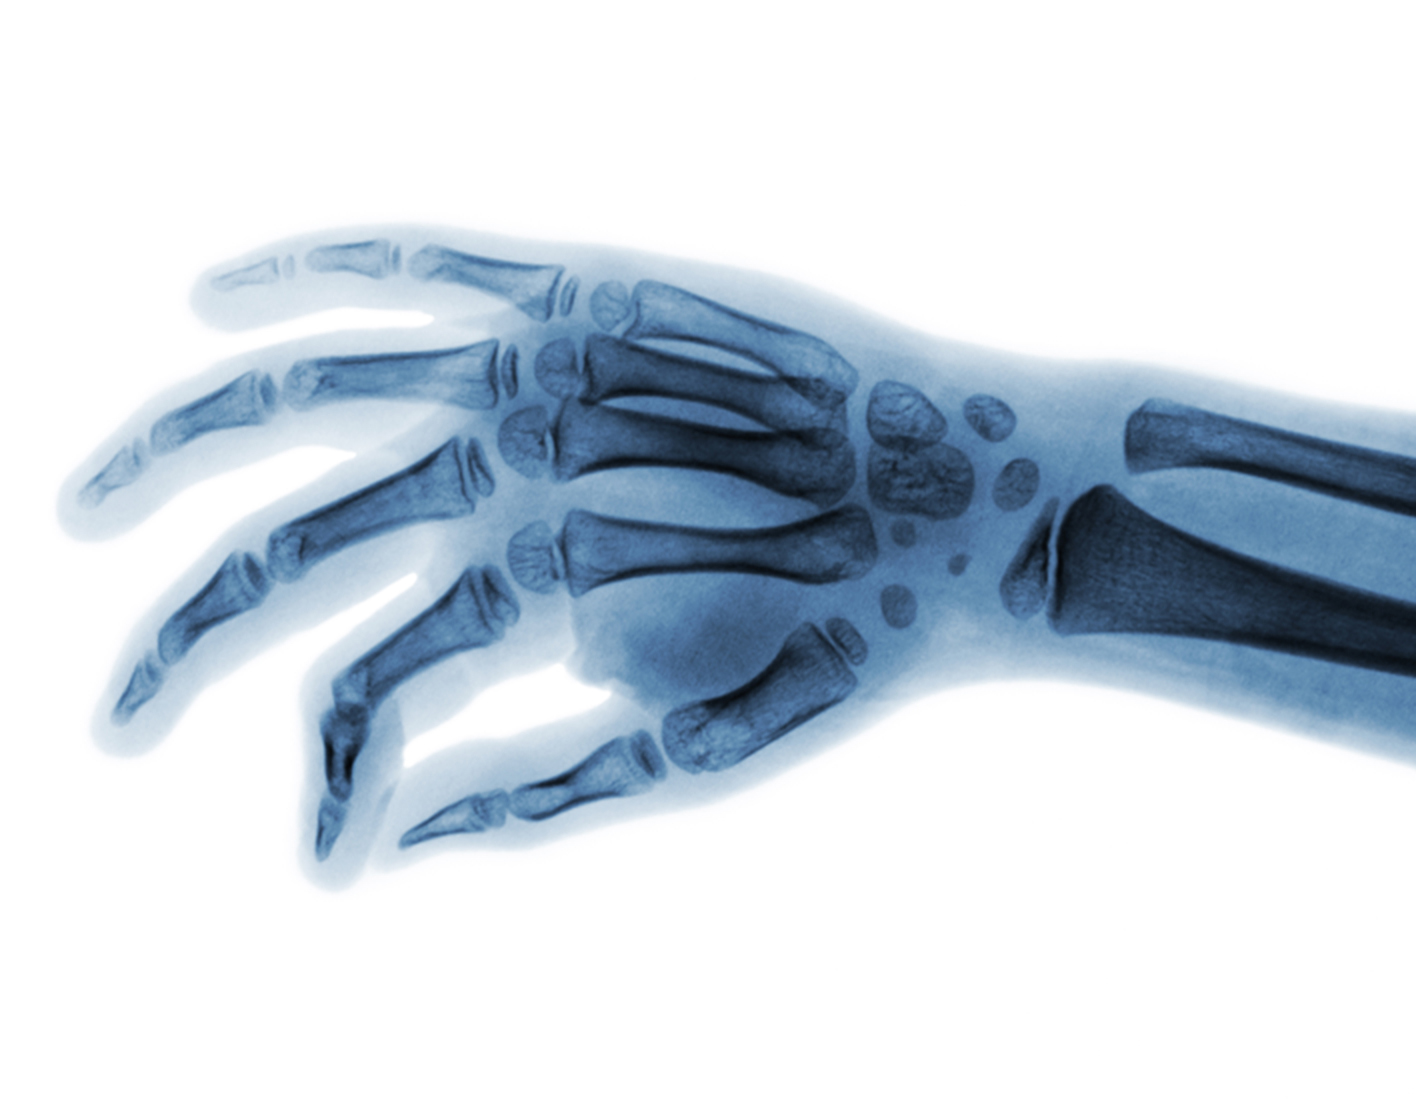

Extremity x-ray

X-rays are a form of radiation that passes through the body to form an image on film. Structures that are dense (such as bone) will appear white. Air will be black, and other structures will be shades of gray.